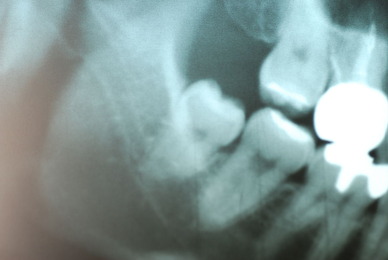

お口の中から差し歯、入れ歯、詰め物を追放しましょう!

口の中の病気を治し、病気を興さない医療を目指します。